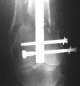

KEMMD> Again, Locking Plating is minimally invasive, SUBCUTANEOUS

KEMMD> INTERNAL FIXATION

Characteristic of locking nailing hardly ever sounds less attractive...

KEMMD> and I believe for the most surgeons preferred

KEMMD> method of treatment for distal femur fractures

A new toy is more interesting and fashionable. And anyway it is not panacea, i have already seen presentations with LISS failures like the attached one presented by D.Seligson. And people also demonstrated incisions say that the method is not so LESS invasive as it supposed to be.